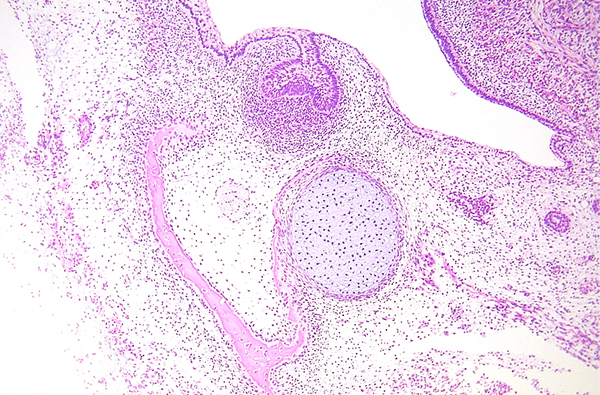

受精卵から(あるいは受精卵の前の精子や卵子を形成する段階から)細胞、組織、臓器が作られていく過程を明らかにするのが発生学であり、できあがった細胞、組織、臓器の微細構造を、光学顕微鏡や電子顕微鏡をもちいて明らかにするのが組織学です。

- 組織学:ヒトの体の細胞、組織や臓器の構造について顕微鏡レベルで学びます。

- 口腔組織学:歯科医師にとって特に重要になる、歯や歯周組織を含めた口腔・顎顔面領域の構造物について、顕微鏡レベルでの構造について学びます。

光学顕微鏡や電子顕微鏡を使った形態学的な方法、構造物の構成物質や分子を解析する方法、遺伝子やタンパク質を検出する分子生物学的な方法など、形態学的な研究手法にとらわれず、種々の方法を用いて研究を行っています。講座の研究テーマの他に、国内外の大学や研究機関とも共同研究を行っています。本講座で実施している主な研究は以下になります。